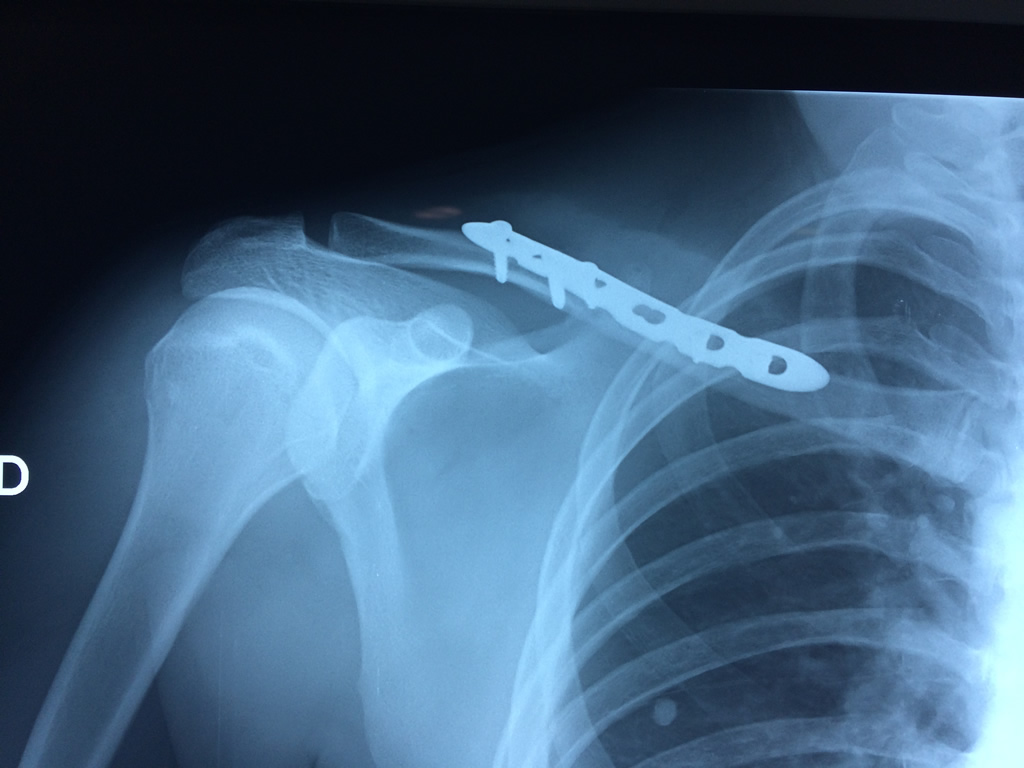

Cirugías de Calcaneo - Clavícula

La clavícula es un hueso largo, con forma de "S" itálica, situado en la parte anterosuperior del tórax. Junto con la escápula forman la cintura escapular. Se puede palpar por toda su longitud y se extiende del esternón al acromion de la escápula, siguiendo una dirección oblicua lateral y posterior.